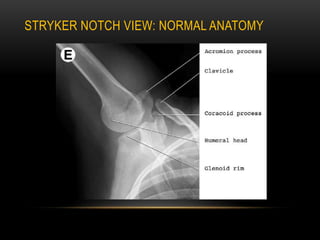

Stryker View Shoulder

Shoulder (Stryker notch view) | Radiology Reference Article | Radiopaedia.org West point and Stryker notch views for anterior shoulder dislocations (animated) - YouTube G. Stryker notch view. | Download Scientific Diagram a Patient position for the Stryker notch view. b Radiograph of Stryker... | Download Scientific Diagram | Stryker View Shoulder